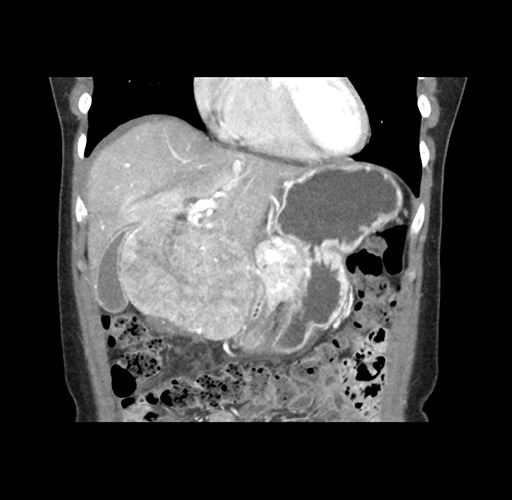

Imaging Analysis

Look through the patient's CT scan to identify any areas of concern for the necessary procedure.

Based on your CT findings, which issue(s) would give reason for "planned slowing down moment(s)" in this case?

Considering a standard left lateral sectionectomy procedure, what step(s) of the operation would you do differently in this case ?